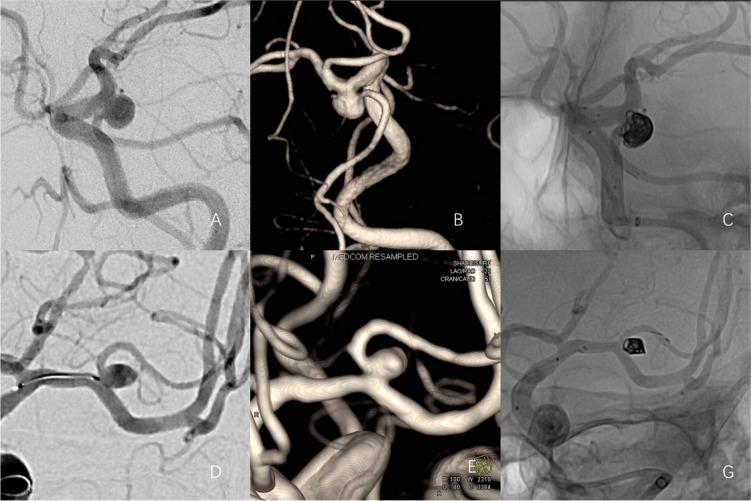

Background: Although stent-assisted coiling has become a standard approach for treating intracranial aneurysms (IAs), there are limited reports on its safety and effectiveness in parent artery less than 2.5 mm in diameter. This study evaluates the feasibility, safety, and short-term outcomes of using Neuroform Atlas stent-assisted coiling for IAs with small parent vessels.

Methods: This study reviewed and analyzed the clinical data of 50 IAs in 50 patients with a parent artery diameter of ≤ 2.5 mm, treated with Neuroform Atlas stent-assisted coiling at a single center between November 2020 and April 2024. Immediate postoperative angiographic outcomes were assessed using the modified Raymond-Roy classification. Follow-up imaging included computed tomographic angiography (CTA), magnetic resonance angiography (MRA), and digital subtraction angiography (DSA). Clinical outcomes were evaluated using the modified Rankin Scale (mRS).

Results: The procedures achieved a 100% success rate. Immediately after treatment, 24 cases were classified as Raymond-Roy grade I, 11 as grade II, and 15 as grade III. Follow-up angiography in 28 cases revealed three instances of aneurysm recurrence, with a secondary procedure performed in one case. One patient reported poor neurological status, and two cases experienced procedure-related adverse events during telephone or clinical follow-up. Conclusions the Atlas stent demonstrated favorable outcomes in the treatment of aneurysms in small parent arteries (< 2.5 mm), with a low complication rate. The timely postoperative use of tirofiban may further reduce the risk of ischemic complications.